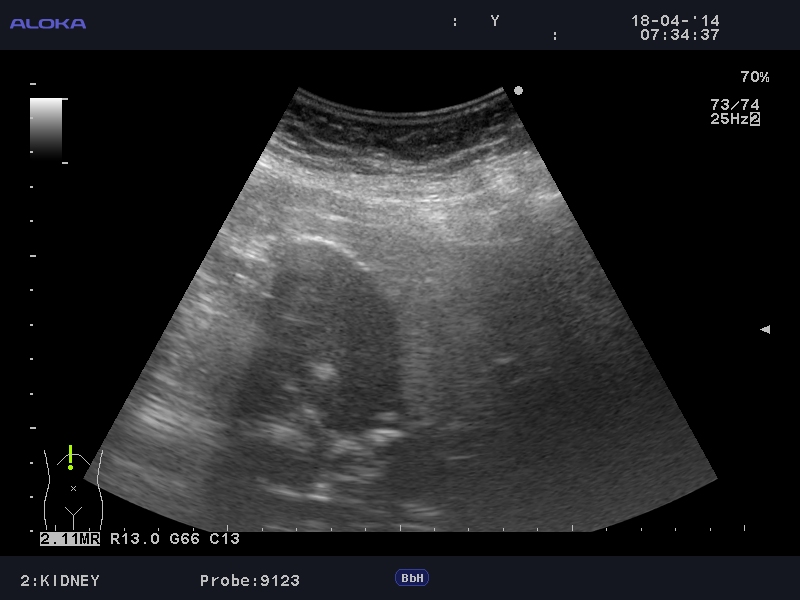

Еще случай.

Бабушка из отделения сестринского ухода, без жалоб на боли в животе. Лаб. анализы не изменены.

Если кальциноз стенки полный и содержимое пузыря осмотру не доступно, то есть показания к проведению КТ-МРТ. Если стенки инкрустированы частично (как в представленных случаях) и можно оценить характер содержимого и структуру стенок, то можно ограничиться только УЗИ. Далее, если есть подозрение на опухоль то пациента направляют к онкологу, а он сам определяет дальнейшую тактику.

Это форма хронического холецистита с кальцификацией стенки ЖП. Термин "фарфоровый" отражает голубоватый оттенок и хрупкую консистенцию ЖП. У мужчин возникает в 5 раз чаще. Кальцификация стенки представляет собой либо непрерывную кальцификацию мышечного слоя, либо прерывистую кальцификацию слизистой и подслизистой. У таких больных высока частота возникновения рака ЖП (11-33%) Каждый раз, когда при УЗИ имеется подозрение на фарфоровый ЖП, для подтверждения диагноза и оценки степени злокачественности проводят КТ